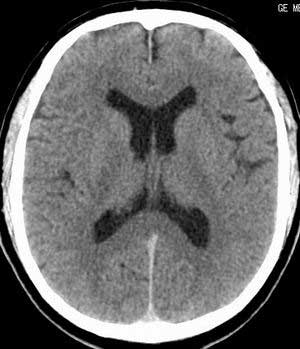

患者男,58岁。耳爆震伤后耳聋2年余,而后双耳道肿胀,间断性流脓。近一月来头痛、恶心、呕吐,右眼红痛,不能入眠。

脑实质密度均匀,未见异常密度灶,脑沟裂池室形态大小正常,中线结构居中.

正常头颅ct表现

正常颅脑ct

颅脑平扫未见异常

正常颅脑ct片。

颅内未见异常,属正常头颅ct表现,建议薄层扫描内耳。